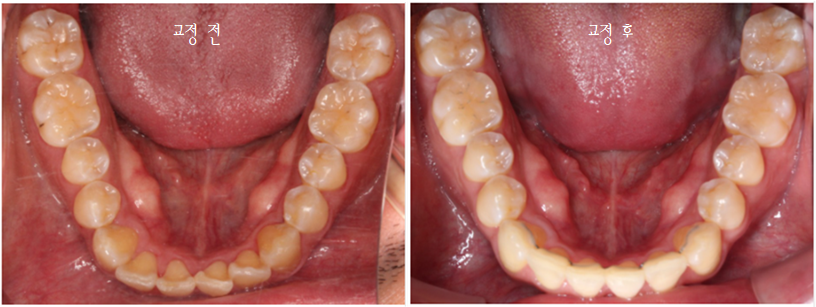

첫 방문 때 이렇게 아래 앞니도 깨져있고,

#12 치아는 안으로 들어가 있었습니다.

환자분은 #13 이 튀어나왔다고 생각하시던데,

이렇게 씹는 면 사진으로 보면

#13이 튀어나왔다라기보단

#12가 상대적으로 들어가 있는 게 맞죠.

아래 앞니도 공간이 부족해서

약간 삐뚤빼뚤한 모습이 나타나지만

충분히 비발치 부분교정으로

펼칠 수 있는 케이스라 판단했습니다.

배열이 처음보다 훨씬 좋아졌습니다.

차이가 조금 더 느껴지실까요 ?^^

마찬가지로 좌 before, 우 after입니다.

이렇게 보면 훨씬 개선된 것이 눈에 띄시죠?^^